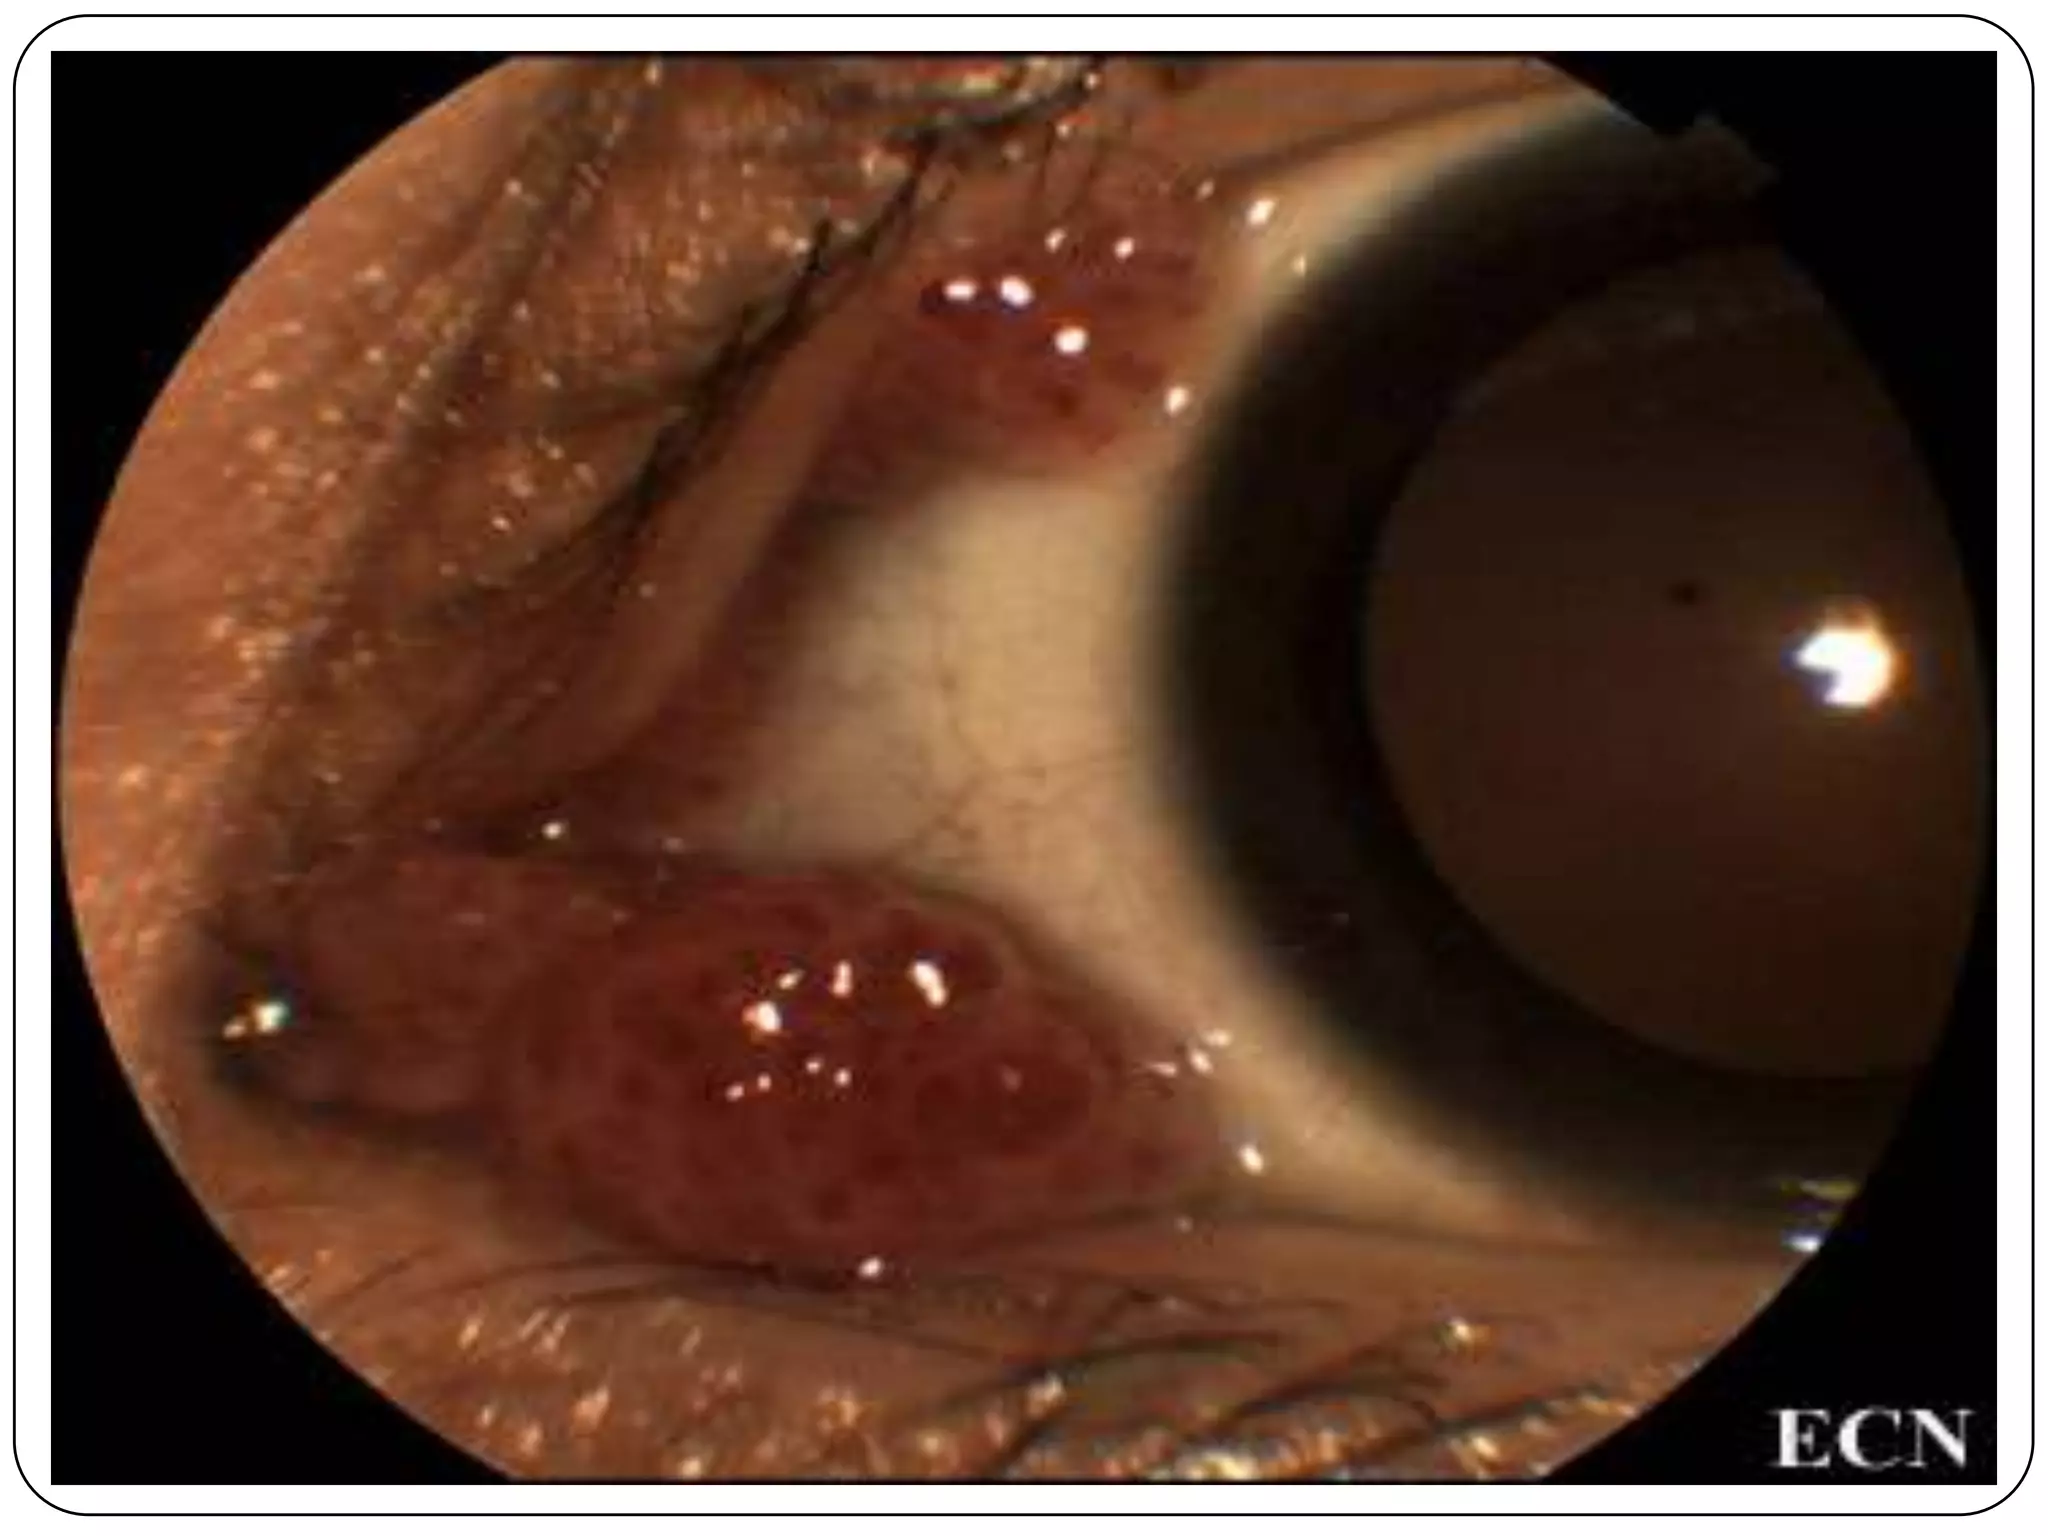

Conjunctival Intraepithelial Neoplasia

(CIN)

Conjunctival Intraepithelial Neoplasia (CIN) Bowen‟s disease  Conjunctival dysplasia  Intraepithelial epithelioma  Dyskeratosis

Etiology of CIN Uncertain, usually unilateral in fair-skinned men in mid 60‟s  Smoking  Human Papillo Virus (HPV)

Management and Treatment Local excision and Cryotherapy with double or triple freeze-thaw  Interferon

Invasive Squamous CellCarcinoma  Replacement of normal epithelium by bizarre pleomorphic cells  10-40% recurrence

Less Common Neoplasmsof the Conjunctiva  Mucoepidermoid Carcinoma (anywhere from the conjunctiva)  Spindle Cell Carcinoma  Sebaceous Cell Carcinoma (50- 60% Upper lids, 20% Lower lids) Asians  Melanocytic Tumors